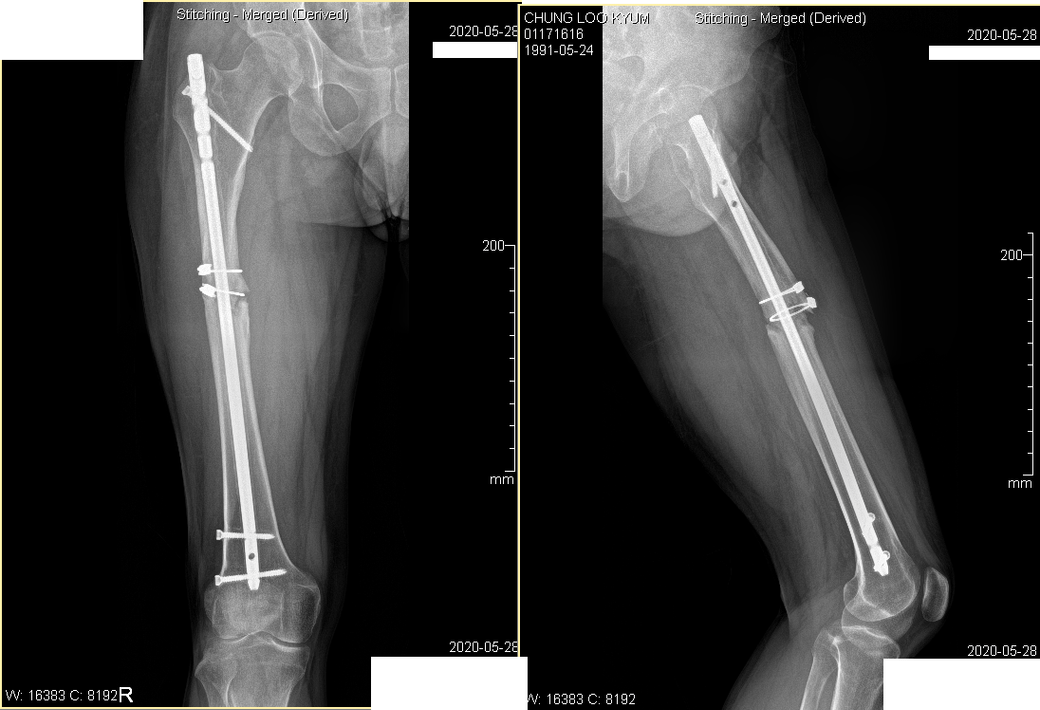

2016년 11월 대퇴부골절

2017년 / 2020 년 사진입니다.

• 2번 째 사진

사진으로도 약간은 어긋난 상태로 아문 것이 사실이지만 이미 시간이 5년이

2. 엑스레이상 보면 대퇴골 중간에 불유합부위가 보이는데 이로 인해 대퇴골이 일직선이 아니고 삐뚤어져있습니다. 이게 통증을 유발하는지는 정형외과 선생님에게 물어보셔야겠습니다.